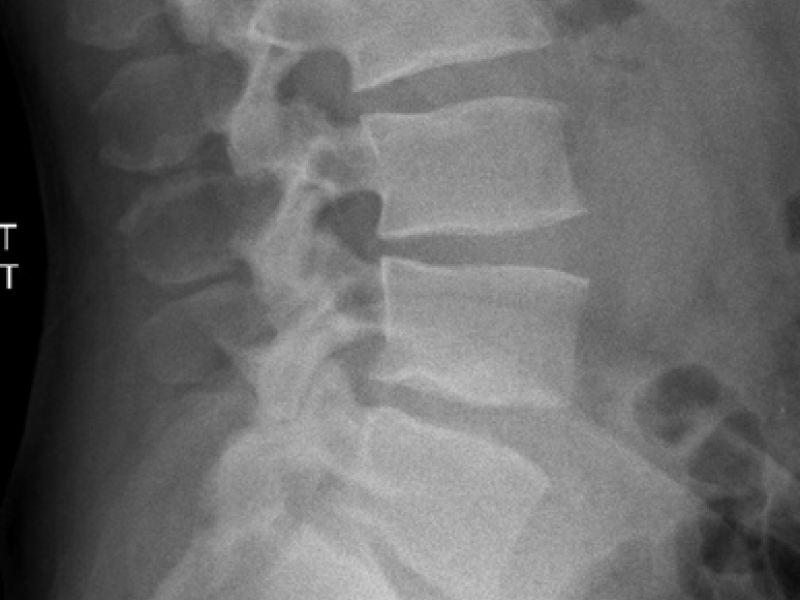

Critical Cases - Back Pain Nightmare Diagnosis!

March 02 2021

History 44 yo male construction worker presents with 2 days